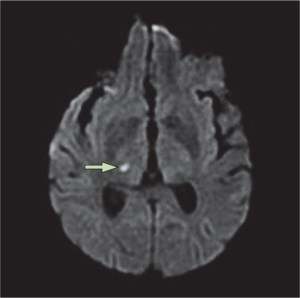

My first post-stroke MRI revealed extensive damage to my right parietal lobe, the area of my brain that controls an integrates muscle movement in the left side of the body (among other things). However, small areas of my frontal lobe also were damaged. This damage, as with the damage to my parietal lobe, occurred without warning, creating what one radiologist characterized to me as “chaos within the brain.